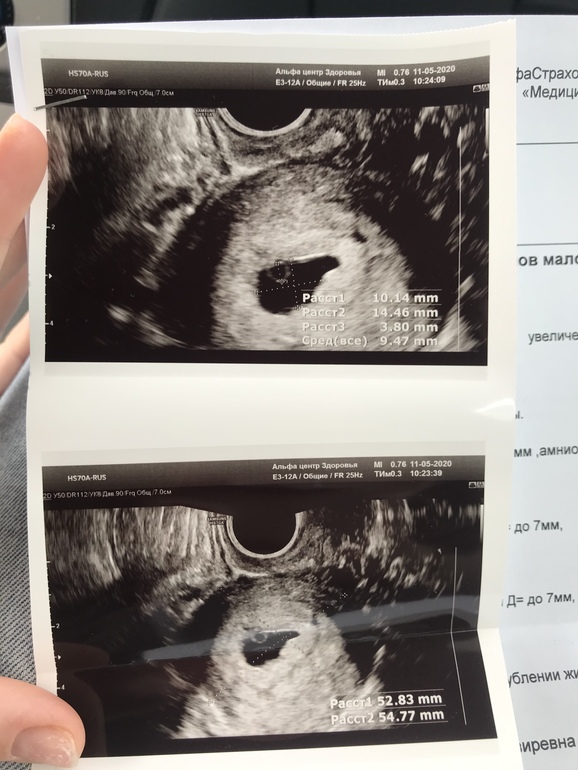

Вот у меня от последних М вчера было 6 недель ровно, а по узи поставили 5

Это что значит, плод отстаёт на неделю или как они по узи определяют недели

Хгч сдавала 7 мая был 12600, что соответствует 4 недели С чем-то

Получается по узи верно

Вам на УЗИ срок не поставили, пока эмбриона нет, будут писать "малого срока". Но для сравнения у меня в 5 акушерская недель плодное яйцо было в 2 раза меньше вашего, а пошла в 7 недель, был эмбрион и сердцебиение, там поставили срок 7 недель.

По замерам эмбриона точный срок скажут, я так понимаю,еще только ПЯ увидели? Приблизительно написали

У меня тоже до того ,как увидели написали примерно 4-5 недель, по ПЯ. Потом в 7 недель пошла,померили эмбрион и точный срок сказали